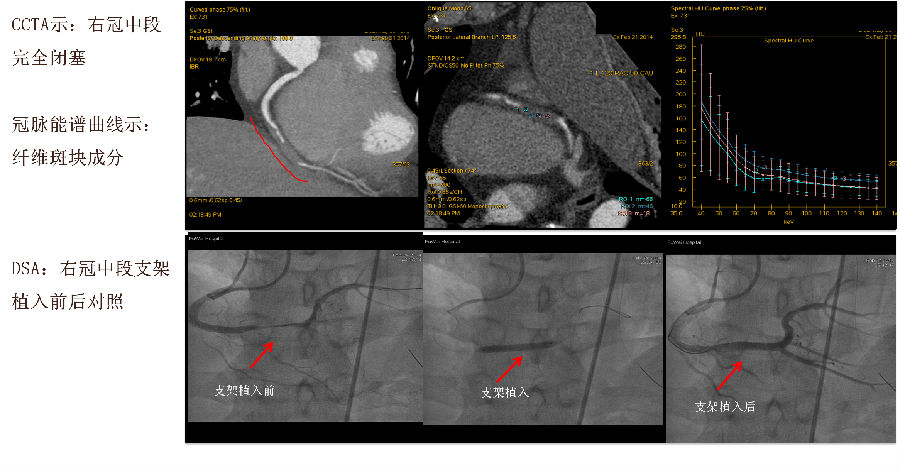

病例展示:Tree VR+融合图像

病例展示:曲面重建、能谱分析、DSA图像

CT表现 右冠(RCA)中段完全闭塞 GSI Myocardium Perfusion:左室下壁及部分外侧壁血流灌注降低